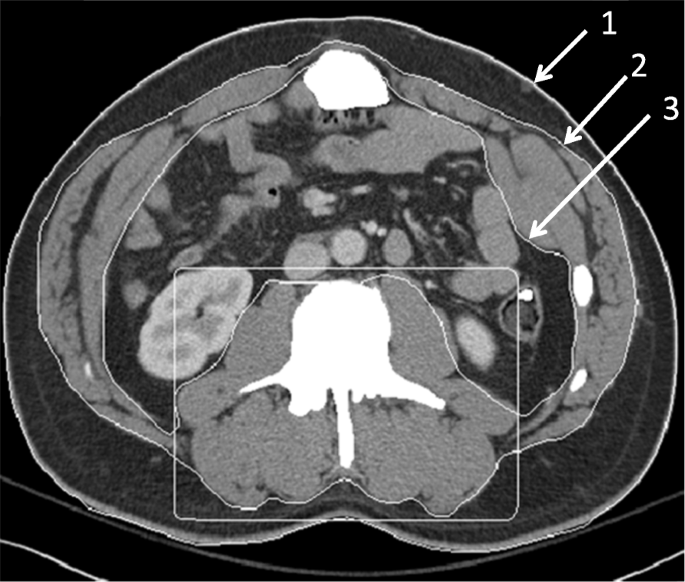

Body composition measurements

Example of segmentation of a computed tomography image with boundary lines between external air and subcutaneous fat (1), between subcutaneous fat and abdominal wall/paraspinal muscles (2), and between abdominal wall/paraspinal muscles and visceral fat (3). The box around the paraspinal muscles allows the algorithm to separately calculate the paraspinal muscle area (if this information is desired)